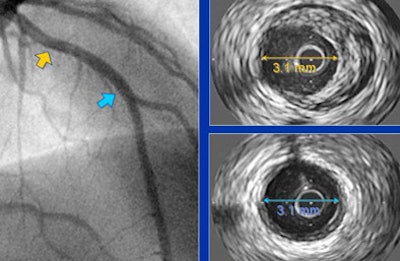

![]() |

| Above and below, patients with normal or near-normal angiographic findings show extensive extraluminal plaque volume at IVUS. |